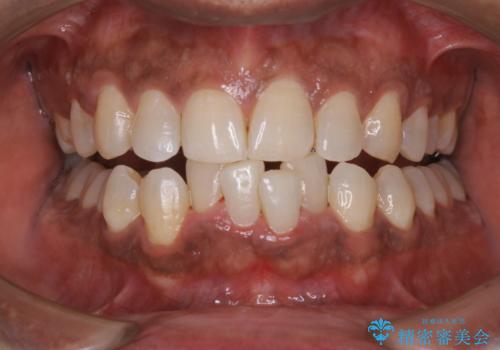

ステインとプラークが内側外側にとても多く付いていました。

タバコも吸うそうで、ステインが多かったです。60分コースでもギリギリ終わるくらいの汚れの量だったため、定期的にクリーニングやメンテナンスを行うようにおすすめしました。